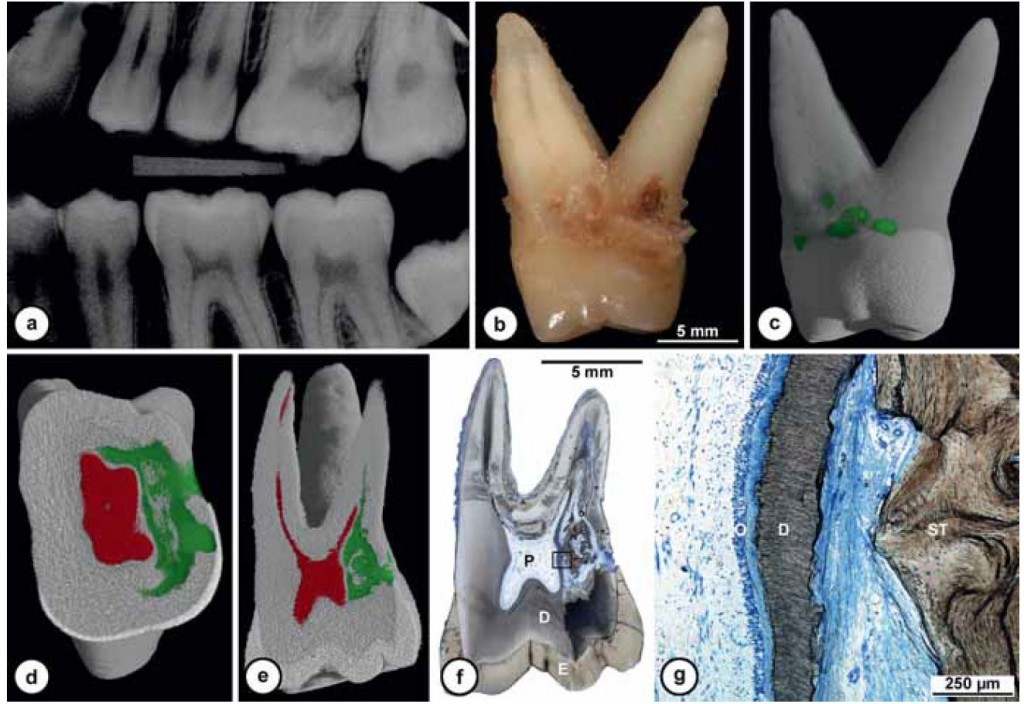

Quando nel 2013 mi è arrivato all’attenzione questo caso

Ho riconosciuto lo stesso fenomeno visto nella ragazza infestata da tessuti alieni di cui sopra e mi sono ricordato che all’università si era parlato di riassorbimenti esterni.

Allora ho studiato il fenomeno e ho saputo fare una diagnosi.

Si trattava di un riassorbimento esterno di classe IV.

Allora per capirci qualcosa in più ho fatto una cone beam.